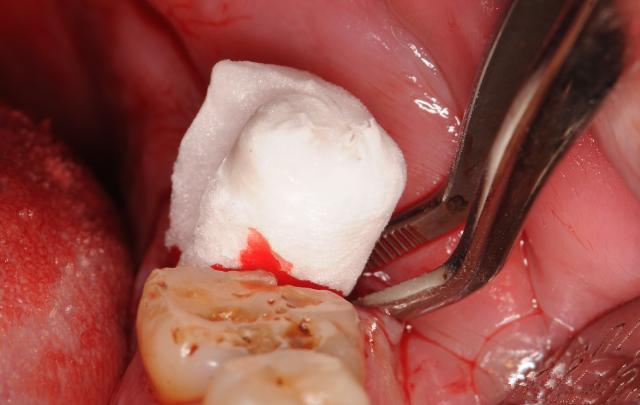

拔牙后常常口中会吐出血丝,不必担忧,这是正常现象,需要注意的是不要破坏口中拔牙后牙槽窝的血块。拔牙后压迫止血用的棉纱卷,在一小时左右吐出,不应过短或过长时间。拔牙后24小时内不刷牙漱口;不做剧烈运动如游泳、打球等;不抽烟饮酒;不要用棉签等硬物擦洗伤口,以免将凝血块破坏、脱落,引起术后出血或伤口感染。